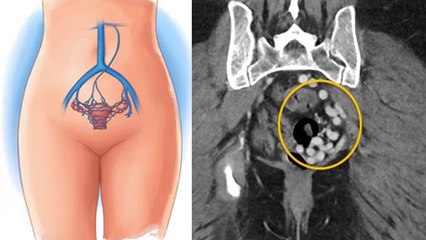

The lower part of the abdomen is called the pelvis or pelvis. This includes the intestines, bladder and ovaries of the lower abdomen. Pelvic pain means pain in any of these organs or the bones or muscles around them.